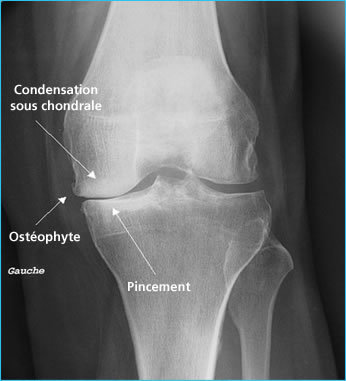

Radiographie standards: signes cardinaux

. pincement de l’interligne articulaire localisé (ET NON DIFFUS -> présent dans l’arthrite)

. ostéophytose

. ostéosclérose sous-chondrale et géodes